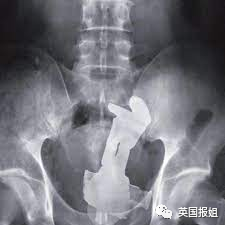

比如风评被害的巴斯光年:

在他X光中,医生们发现了可怜的芭比娃娃,不仅在非常深的地方,而且还双臂高举,头发散乱。

按这位网友的话说:“她看起来真的很开心呢!”